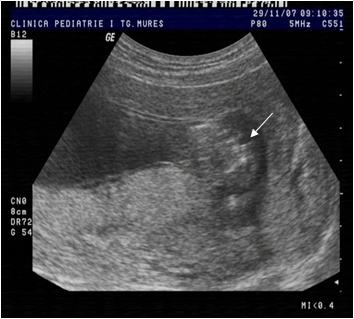

Fig. nr.123 Hernie fiziologica la 11 saptamani, fat in sectiune longitudinala.

( sageata)

Fig. nr.124 Hernia fiziologica fetala in sectiunea transversala abdominala.